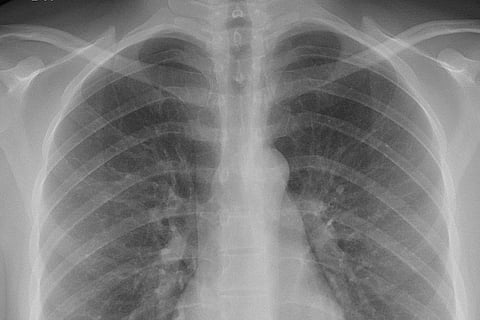

एक्स-रे की खोज 1895 में जर्मनी के वुर्जबर्ग विश्वविद्यालय के प्रोफेसर विल्हेम कॉनराड रॉन्टगन द्वारा की गई थी। रॉन्टगन अपनी प्रयोगशाला में कैथोड-रे ट्यूब के साथ काम कर रहे थे, जब उन्होंने अपनी ट्यूब के पास एक मेज पर क्रिस्टल की एक फ्लोरोसेंट चमक देखी, जिसमें एक नकारात्मक और सकारात्मक इलेक्ट्रोड वाला बल्ब था।

जब ट्यूब से हवा निकाली गई और उच्च वोल्टेज दिया गया, तो ट्यूब ने एक फ्लोरोसेंट चमक पैदा करना शुरू कर दिया। ट्यूब को काले कागज से ढकते हुए, उन्होंने पाया कि ट्यूब से कुछ फीट की दूरी पर रखी सामग्री से हरे रंग की फ्लोरोसेंट रोशनी उत्पन्न होती है।

इस प्रक्रिया को देखते हुए, उन्होंने निष्कर्ष निकाला कि ट्यूब एक नई प्रकार की किरण उत्सर्जित कर रही थी जो कागज को कवर करने और फॉस्फोरसेंट सामग्री को उत्तेजित करने में सक्षम थी। उन्होंने पता लगाया कि यह नई किरण कई पदार्थों से होकर गुजर सकती है और ठोस वस्तुओं पर छाया डाल सकती है।

रॉन्टगन को यह भी एहसास हुआ कि, किरण मानव ऊतकों से तो गुजर सकती है लेकिन हड्डियों और धातु से नहीं। उनके पहले प्रयोगों में से एक उनकी पत्नी के हाथ की एक फिल्म थी जिसमें उनकी हड्डियां और अंगूठी दिखाई देती हैं।